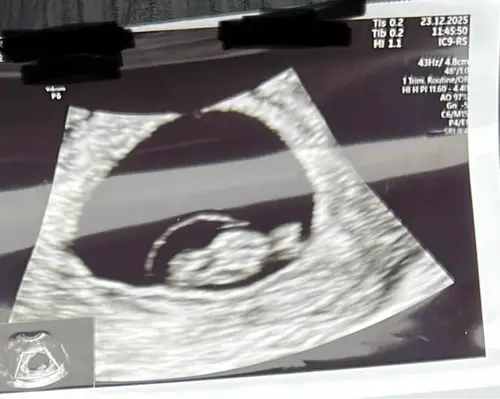

Gister mijn 2e echo gehad. 8 weken 6 dagen, dus nu de 9 aangetikt. De kleine bewoog al lekker door het vruchtwater en een mooi kloppend hartje 😍 over 2 weekjes de termijnecho